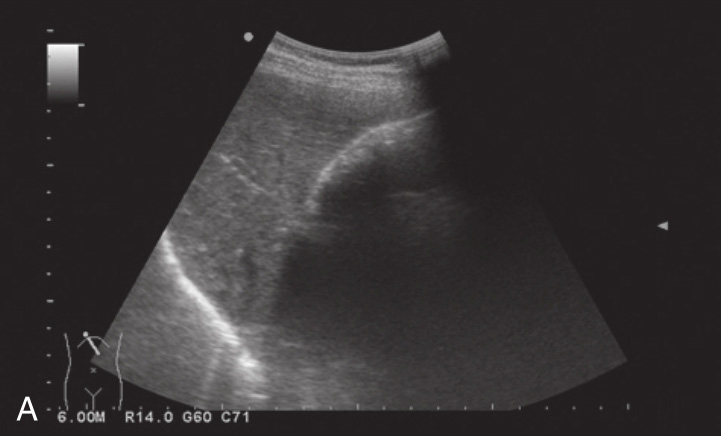

(1)典型胆囊结石

1)胆囊腔内出现团状强回声,一般较大而孤立分布的强回声多呈新月形、半圆形或圆形强回声;体积较小的多发结石,堆积于胆囊后壁时形成一片强回声带,不易分辨结石数目(图2-6-1)。

2)强回声结石后方伴声影(图2-6-2),结石的声影边缘锐利,宽度与结石的宽度基本一致,此特征可与胃肠气体形成的声影相鉴别。

3)强回声结石随体位改变而移动。

图2-6-1 典型胆囊结石灰阶超声图像